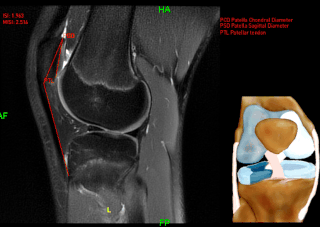

Currently our easily integrable software enables the fully automatic, prompt & robust annotation of the relevant anatomic details and detection of the most frequent knee lesions: ACL & meniscal tears, articular cartilage lesions, patellar instability measurments, Baker cysts.